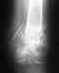

31 декабря упал с горки и получил сложный перелом со смещением

Головка локтевой кости.

Головка плечевой кости.

Головка лучевой кости (раздроблена).

Перелом был осложнен смещением отломков и разрывом суставной сумки.

Было проведено оперативное вмешательство по удалению мелких отломков и резекции головки лучевой кости.